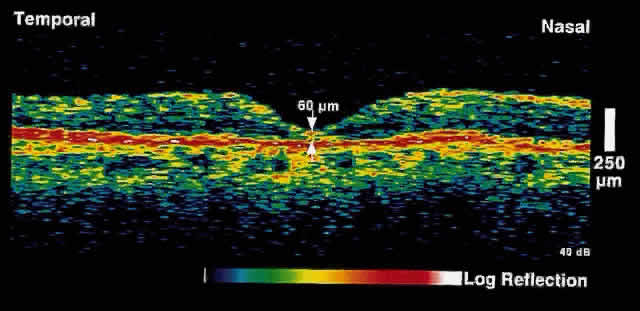

Fig. 6. OCT image through the fovea of the same patient several weeks after focal

laser photocoagulation. Note the dramatic decrease in retinal thickening. Fig. 6. OCT image through the fovea of the same patient several weeks after focal

laser photocoagulation. Note the dramatic decrease in retinal thickening.

|